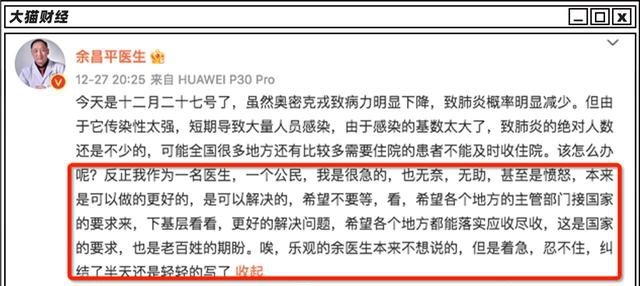

武汉大学人民医院呼吸内科主任余昌平认为,奥密克戎引起肺炎的概率减少,但是因为感染基数太大,导致的肺炎人数还是不少的,“引起的肺炎远高于流感”。

他同时呼吁,地方能够下基层,让需要住院的患者能够被及时收住院,落实“应收尽收”。